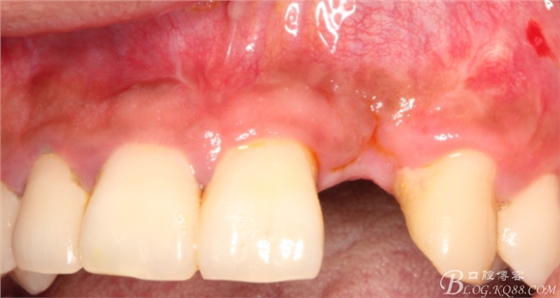

4個(gè)月后,唇側(cè)豐滿度尚可,與鄰牙之間齦乳頭完整。

保留齦乳頭翻小瓣。